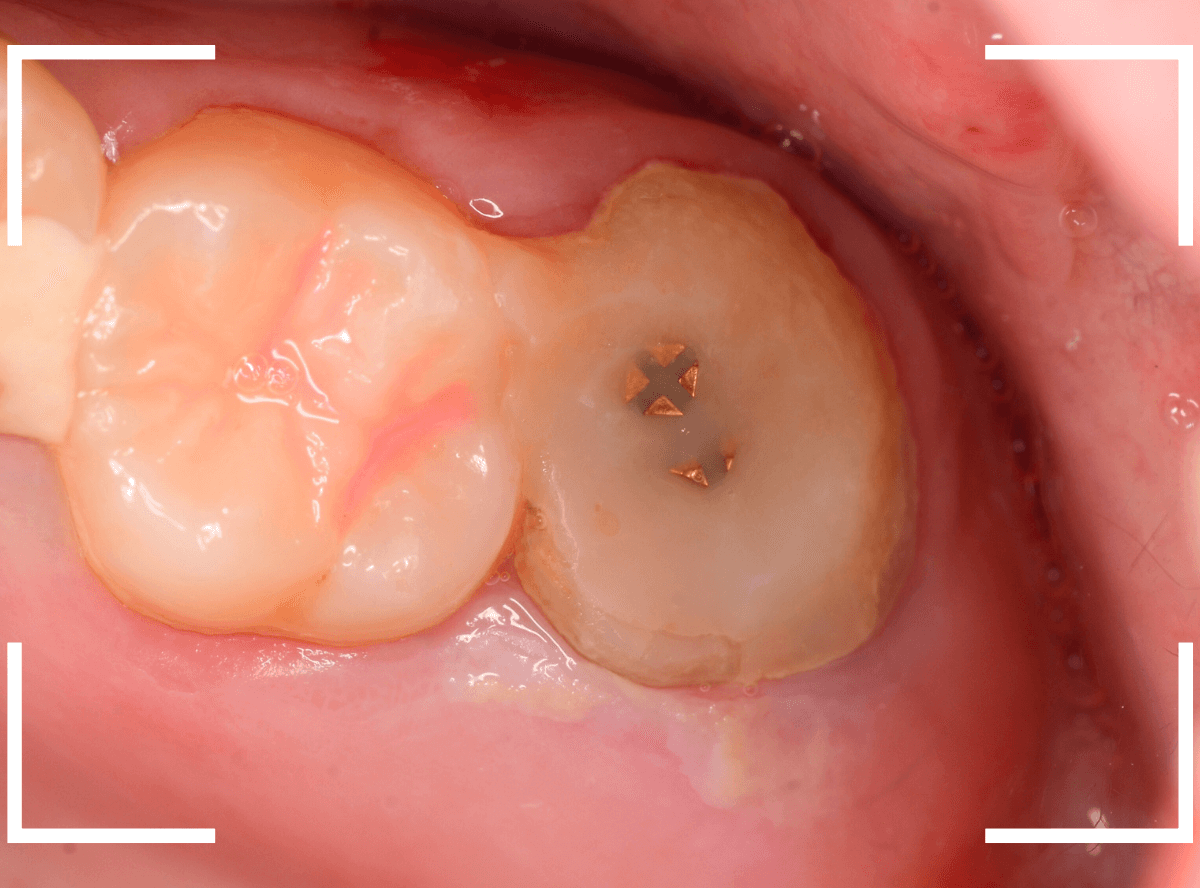

Case.10

さし歯を入れるスペースがない!

一番奥の歯が土台(コア)の治療までで中断してしまってる患者さんの例です。

本来であれば、この上にさし歯を作らなければいけないのですが、この時点でかみ合ってしまい、さし歯を作ろうにも作りづらい状況でうやむやのうちに治療中断になってしまったようです。

まず、土台の治療をしてから時間が経過していることと、不適合になっている事から、外して中を調べます。

すると、土台の中で虫歯にもなっていました。

(〇部の赤い部分)

こういった事は、レントゲン写真でもよくわからない事が多く、土台を外す治療は本当に神経を使います。